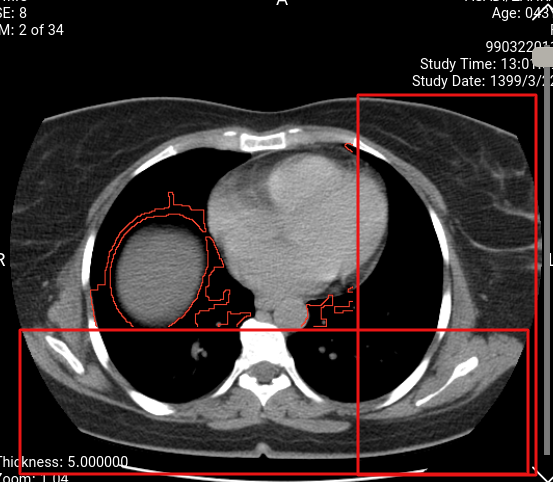

Hi thanks for the excellent work. I have a problem with the overlay show. 1 2 my overlay and my base image (512 x 512), But overlay is displayed up to 370 x 370. These are my objects Overlay: overlayData.overlays.push({ rows: 512, columns: 512, type: '', x: 0, y: 0, pixelData: pixedlData, description: undefined, label: undefined, roiArea: undefined, roiMean: undefined, roiStandardDeviation: undefined, fillStyle: 'red', visible: true }); Image : cachedLut: {lutArray: Uint8ClampedArray(4156), windowWidth: 400, windowCenter: 40, invert: false, voiLUT: undefined, …} color: false columnPixelSpacing: 0.646484 columns: 512 data: n {byteArrayParser: {…}, byteArray: Uint8Array(197792), elements: {…}, warnings: Array(0)} decodeTimeInMS: 78 floatPixelData: undefined getPixelData: ƒ () height: 512 imageId: "" intercept: -1024 invert: false loadTimeInMS: 1492 maxPixelValue: 2155 minPixelValue: -2000 rowPixelSpacing: 0.646484 rows: 512 sharedCacheKey: "" sizeInBytes: 524288 slope: 1 stats: {lastGetPixelDataTime: -1, lastStoredPixelDataToCanvasImageDataTime: -1, lastPutImageDataTime: -1, lastRenderTime: 0.09499999950639904, lastLutGenerateTime: -1} totalTimeInMS: 1573 width: 512 windowCenter: 40 windowWidth: 400

Screenshots

Before before After after